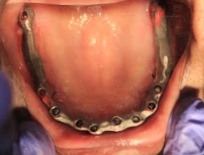

HOW THE All ON FOUR VARIES FROM REMOVABLE DENTURES?